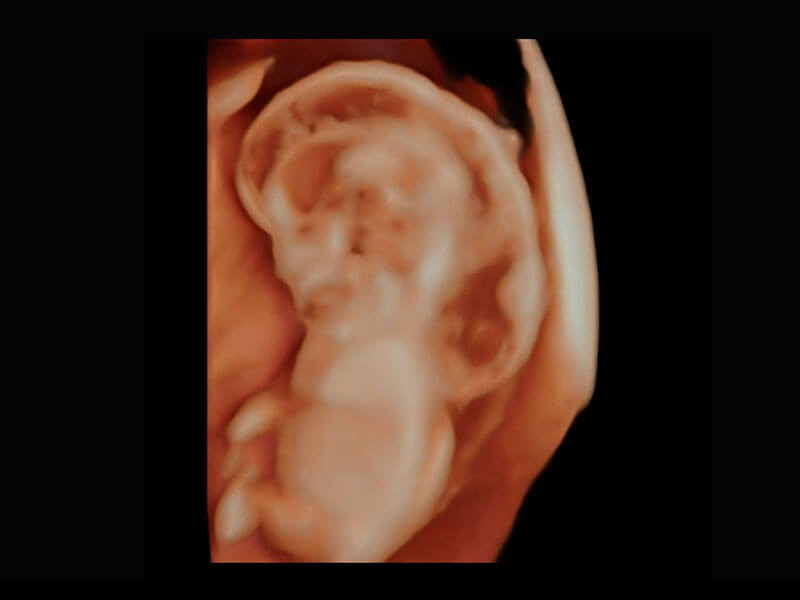

P60在胎兒早孕期超聲篩查中為您帶來優(yōu)異的圖像質(zhì)量。

早孕-胎心

胎兒體循環(huán)